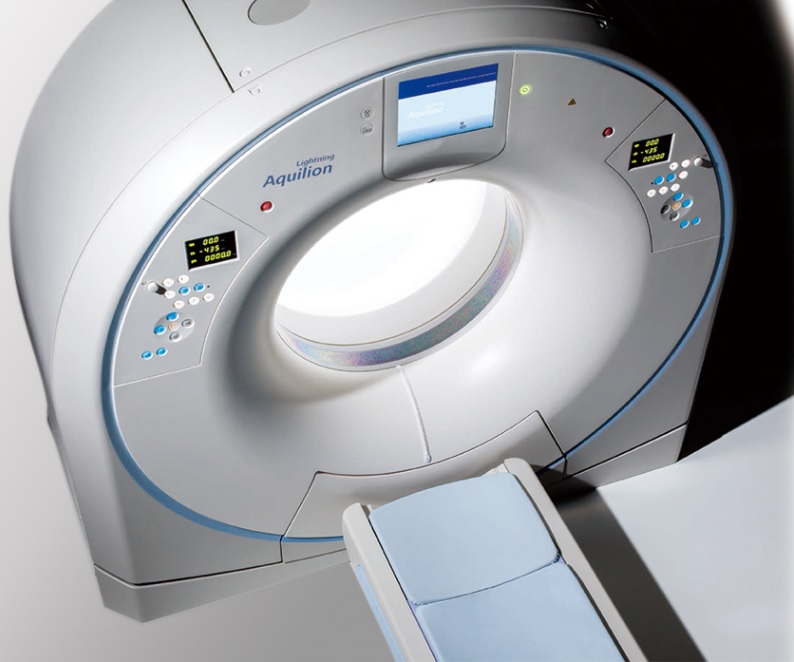

Canon

Canon, Aquilion Lightning, sistema de Tomografía Computada helicoidal de 16 filas de detectores y 32 cortes, para imágenes de cuerpo entero, emplea tecnologías de vanguardia para optimizar la atención al paciente y acelerar la toma de decisiones clínicas. Las características innovadoras aseguran que las imágenes isotrópicas de alta calidad se adquieran de forma rutinaria con dosis bajas para el paciente. El flujo de trabajo se simplifica, aumentando el rendimiento del paciente y cuenta con una amplia gama de aplicaciones avanzadas de procesamiento 3D y postprocesamiento que brindan flexibilidad clínica.

Incluye Inteligencia Artificial AiCE, tecnología avanzada de Reconstrucción de Imágenes por Aprendizaje Profundo, que ha sido entrenada para reducir el ruido y reforzar la información de señal válida, con el objetivo de entregar imágenes claras y definidas a una alta velocidad y con hasta un 82% reducción de dosis (respecto FBP).

Tomografía Computada asistida por Inteligencia Artificial: AiCE

Detector de 0,5 mm, el más fino del mercado

Líder mundial en Detectabilidad de Bajo Contraste con 5mm a 2.6 mGy

La Menor Dosis de radiación a paciente